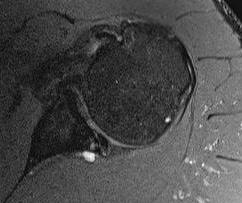

Kim lesion

- Kim lesion

- incomplete and concealed avulsion of the posteroinferior labrum

- superficial portion attached, deep portion detached

- labrum flat with loss of normal height resulting in retroversion of the chondrolabral glenoid

Posterior labral tears + cyst